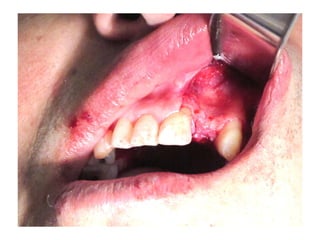

• Paciente de 25 años con

pérdida casi total de

dientes superiores y

prótesis mal adaptada.

• Ganchos que no

cumplen su función.

Modelos de estudio, a la izquierda sin la prótesis a la derecha con la prótesis, el

molar izquierdo con destrucción casi total de la corona y sin utilidad protésica.